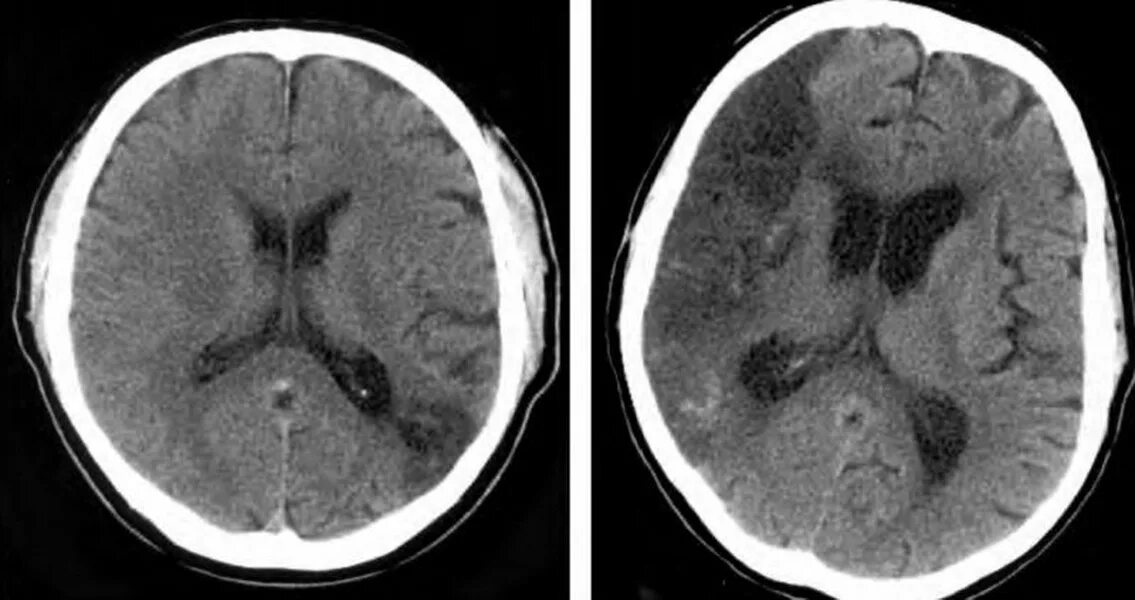

Очагов изменения белого вещества головного мозга